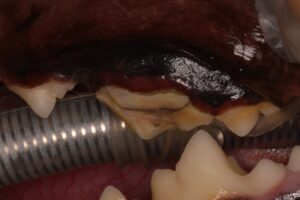

歯の状態

左上顎の8番目の歯が折れてしまい、歯髄(歯の神経・血管)が露出しています。

この状態を放置してしまうと強い痛みや感染、炎症を引き起こすため、抜歯か歯内治療の処置が必要になります。

抜歯をすれば今後の感染や炎症などのリスクをなくすことができます。

こちらのワンちゃんは飼い主さんと相談し、抜歯をすることになりました。

抜歯後の状態

上の写真は抜歯をした後です。

歯肉を縫合しています。